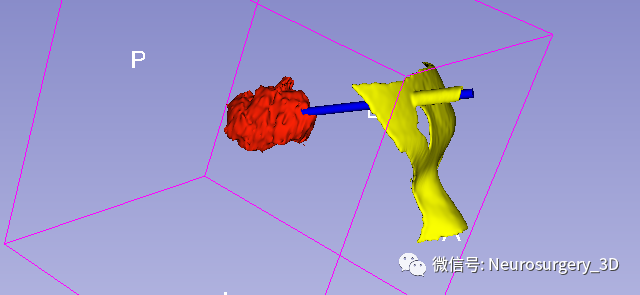

1、利用Ruler测量出穿刺血肿靶点至穿刺外口的距离,并设计出穿刺路径顺血肿长轴走形在血肿中心(并非如下图所示所有穿刺路径均与矢状面平行、请注意穿刺深度),避开颅内重要结构如额窦、上矢状窦等。

透视化血肿状态下显示穿刺路径走形在血肿中心

2、建立穿刺导管